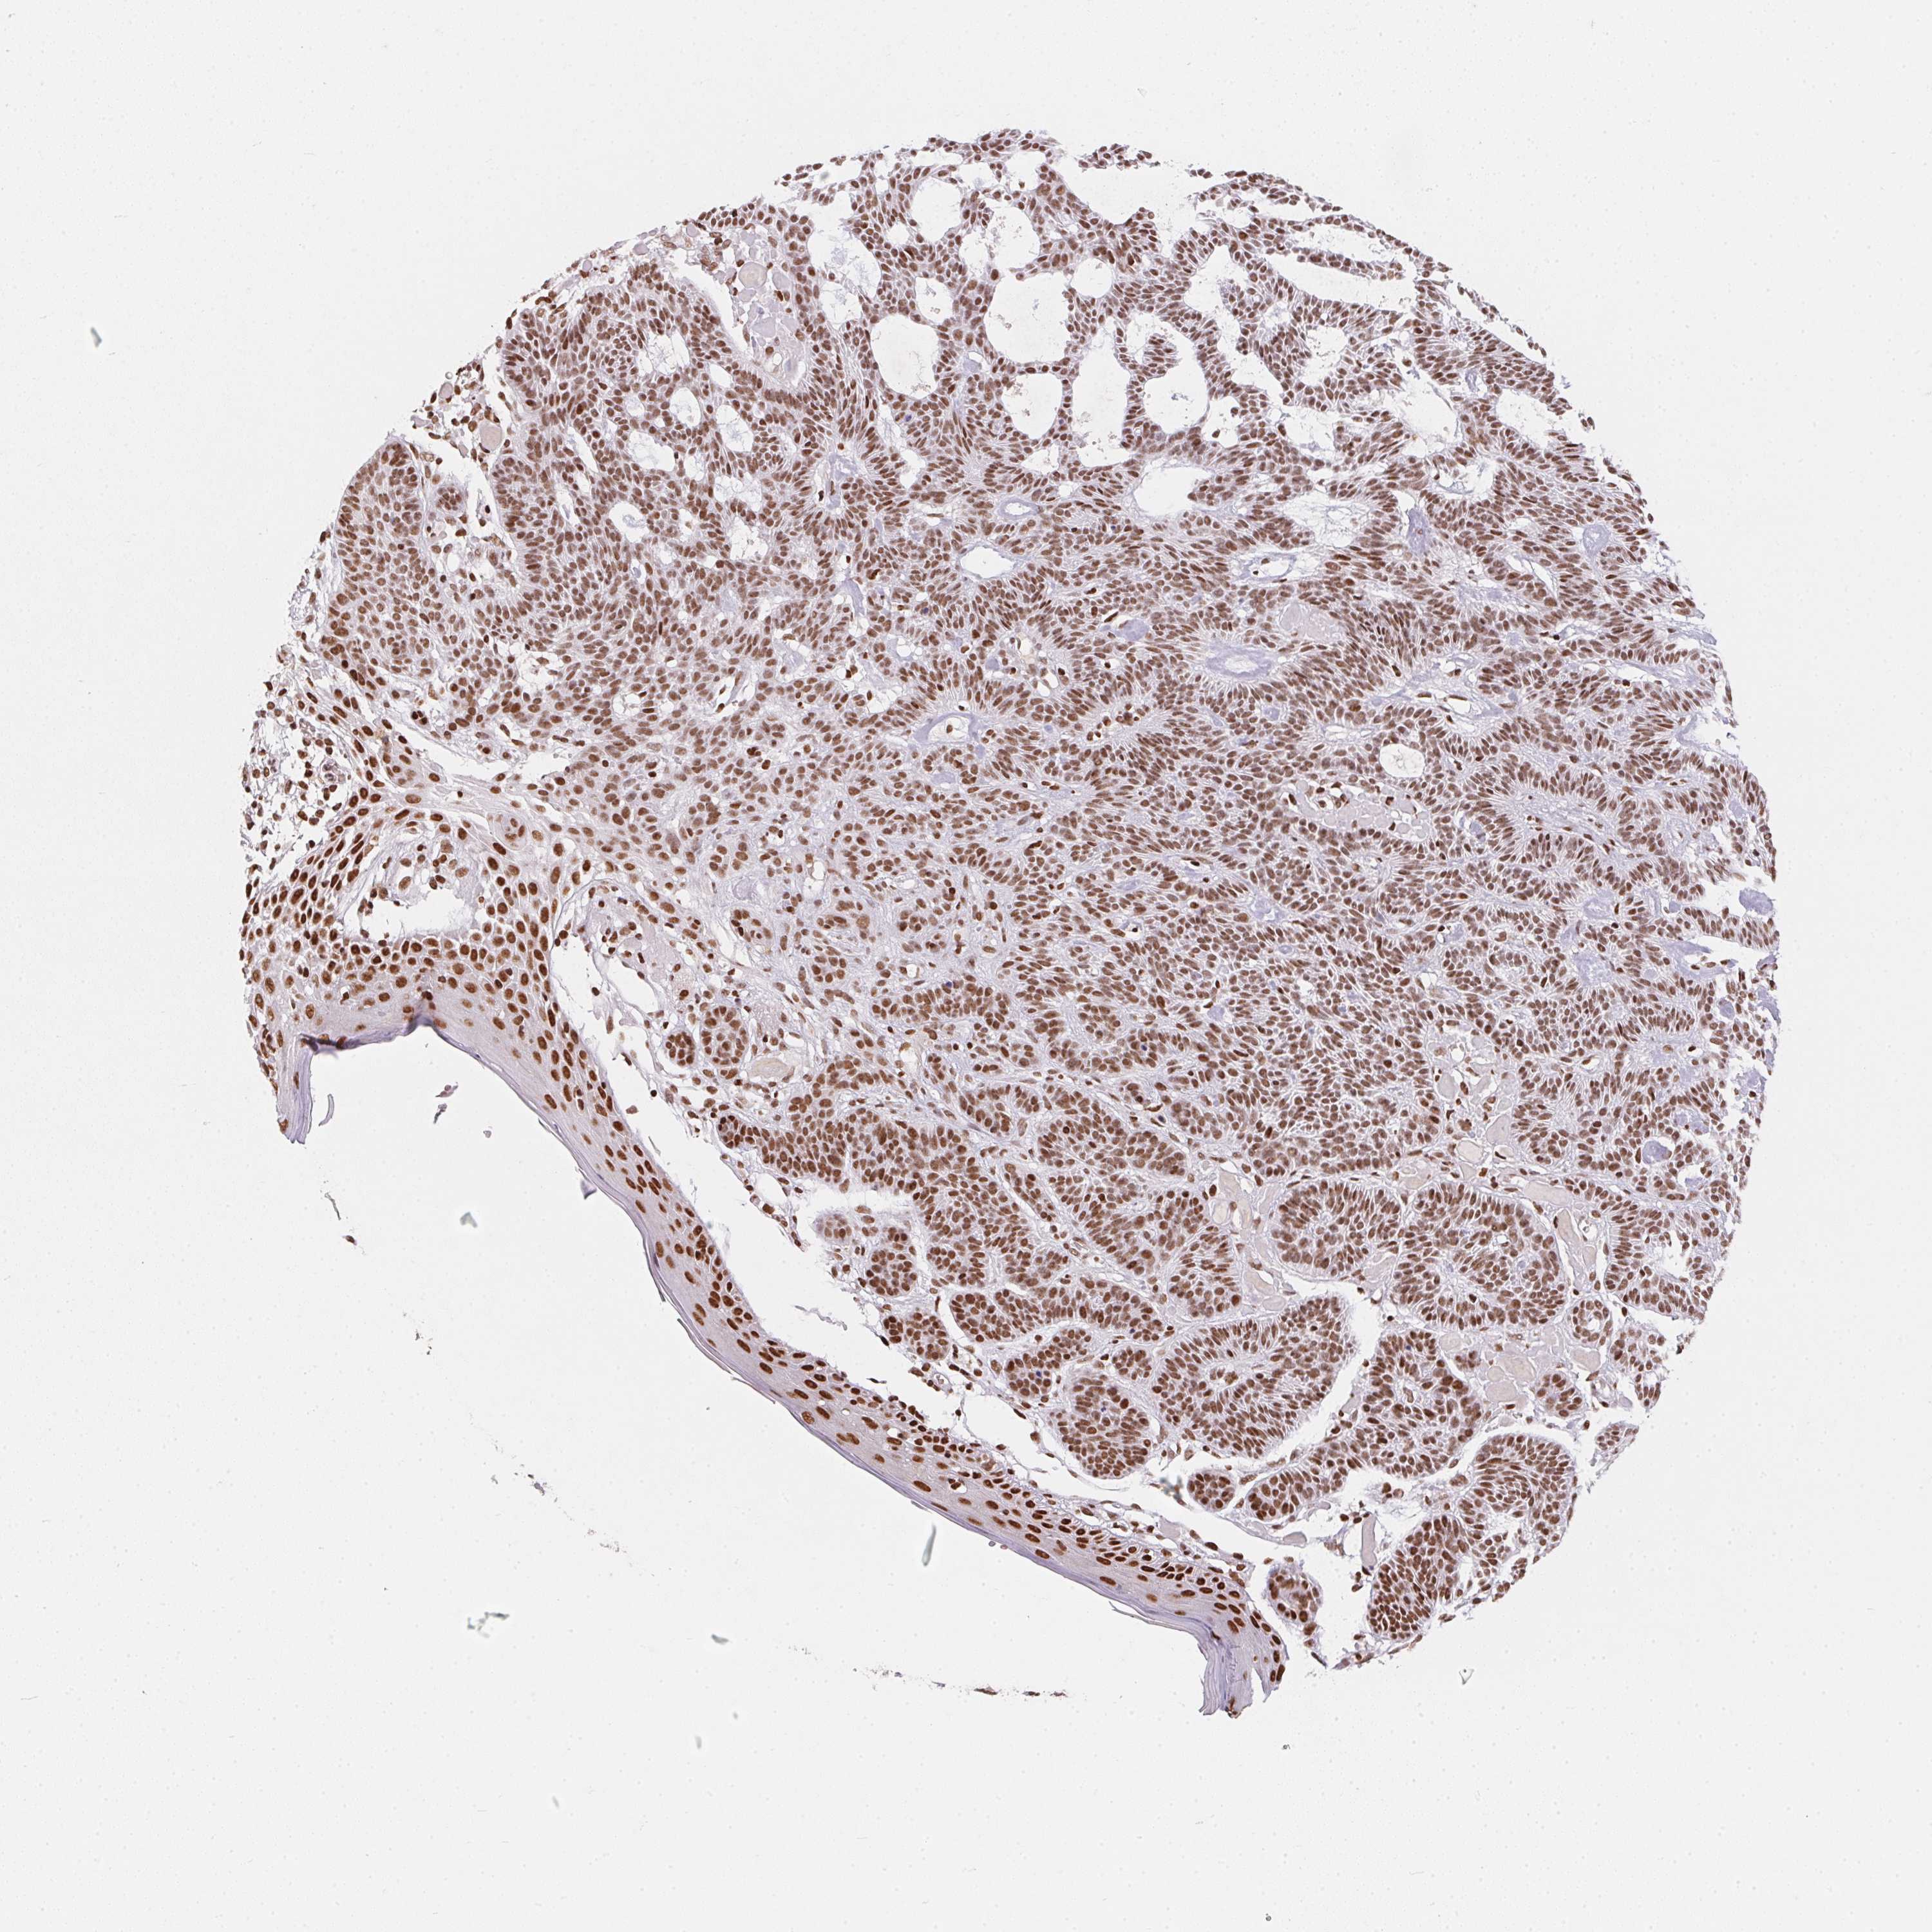

SKIN CANCER - Protein expressioni

A mouse-over function shows sample information and annotation data. Click on an image to view it in a full screen mode. Samples can be filtered based on level of antibody staining by selecting one or several of the following categories: high, medium, low and not detected. The assay and annotation is described here.

Each image is clickable and will lead to virtual microscopy that enables deeper exploration of all samples and also displays staining intensity scores, fraction scores and subcellular localization as well as patient and tissue information for each sample.

Antibody HPA064887

Staining

High

Medium

Low

Not detected

Intensity

Strong

Moderate

Weak

Negative

Quantity

>75%

75%-25%

<25%

None

Location

Nuclear

Cytoplasmic/membranous

Cytoplasmic/membranous,nuclear

Basal cell carcinoma

BCC, high aggressive

Squamous cell carcinoma, NOS